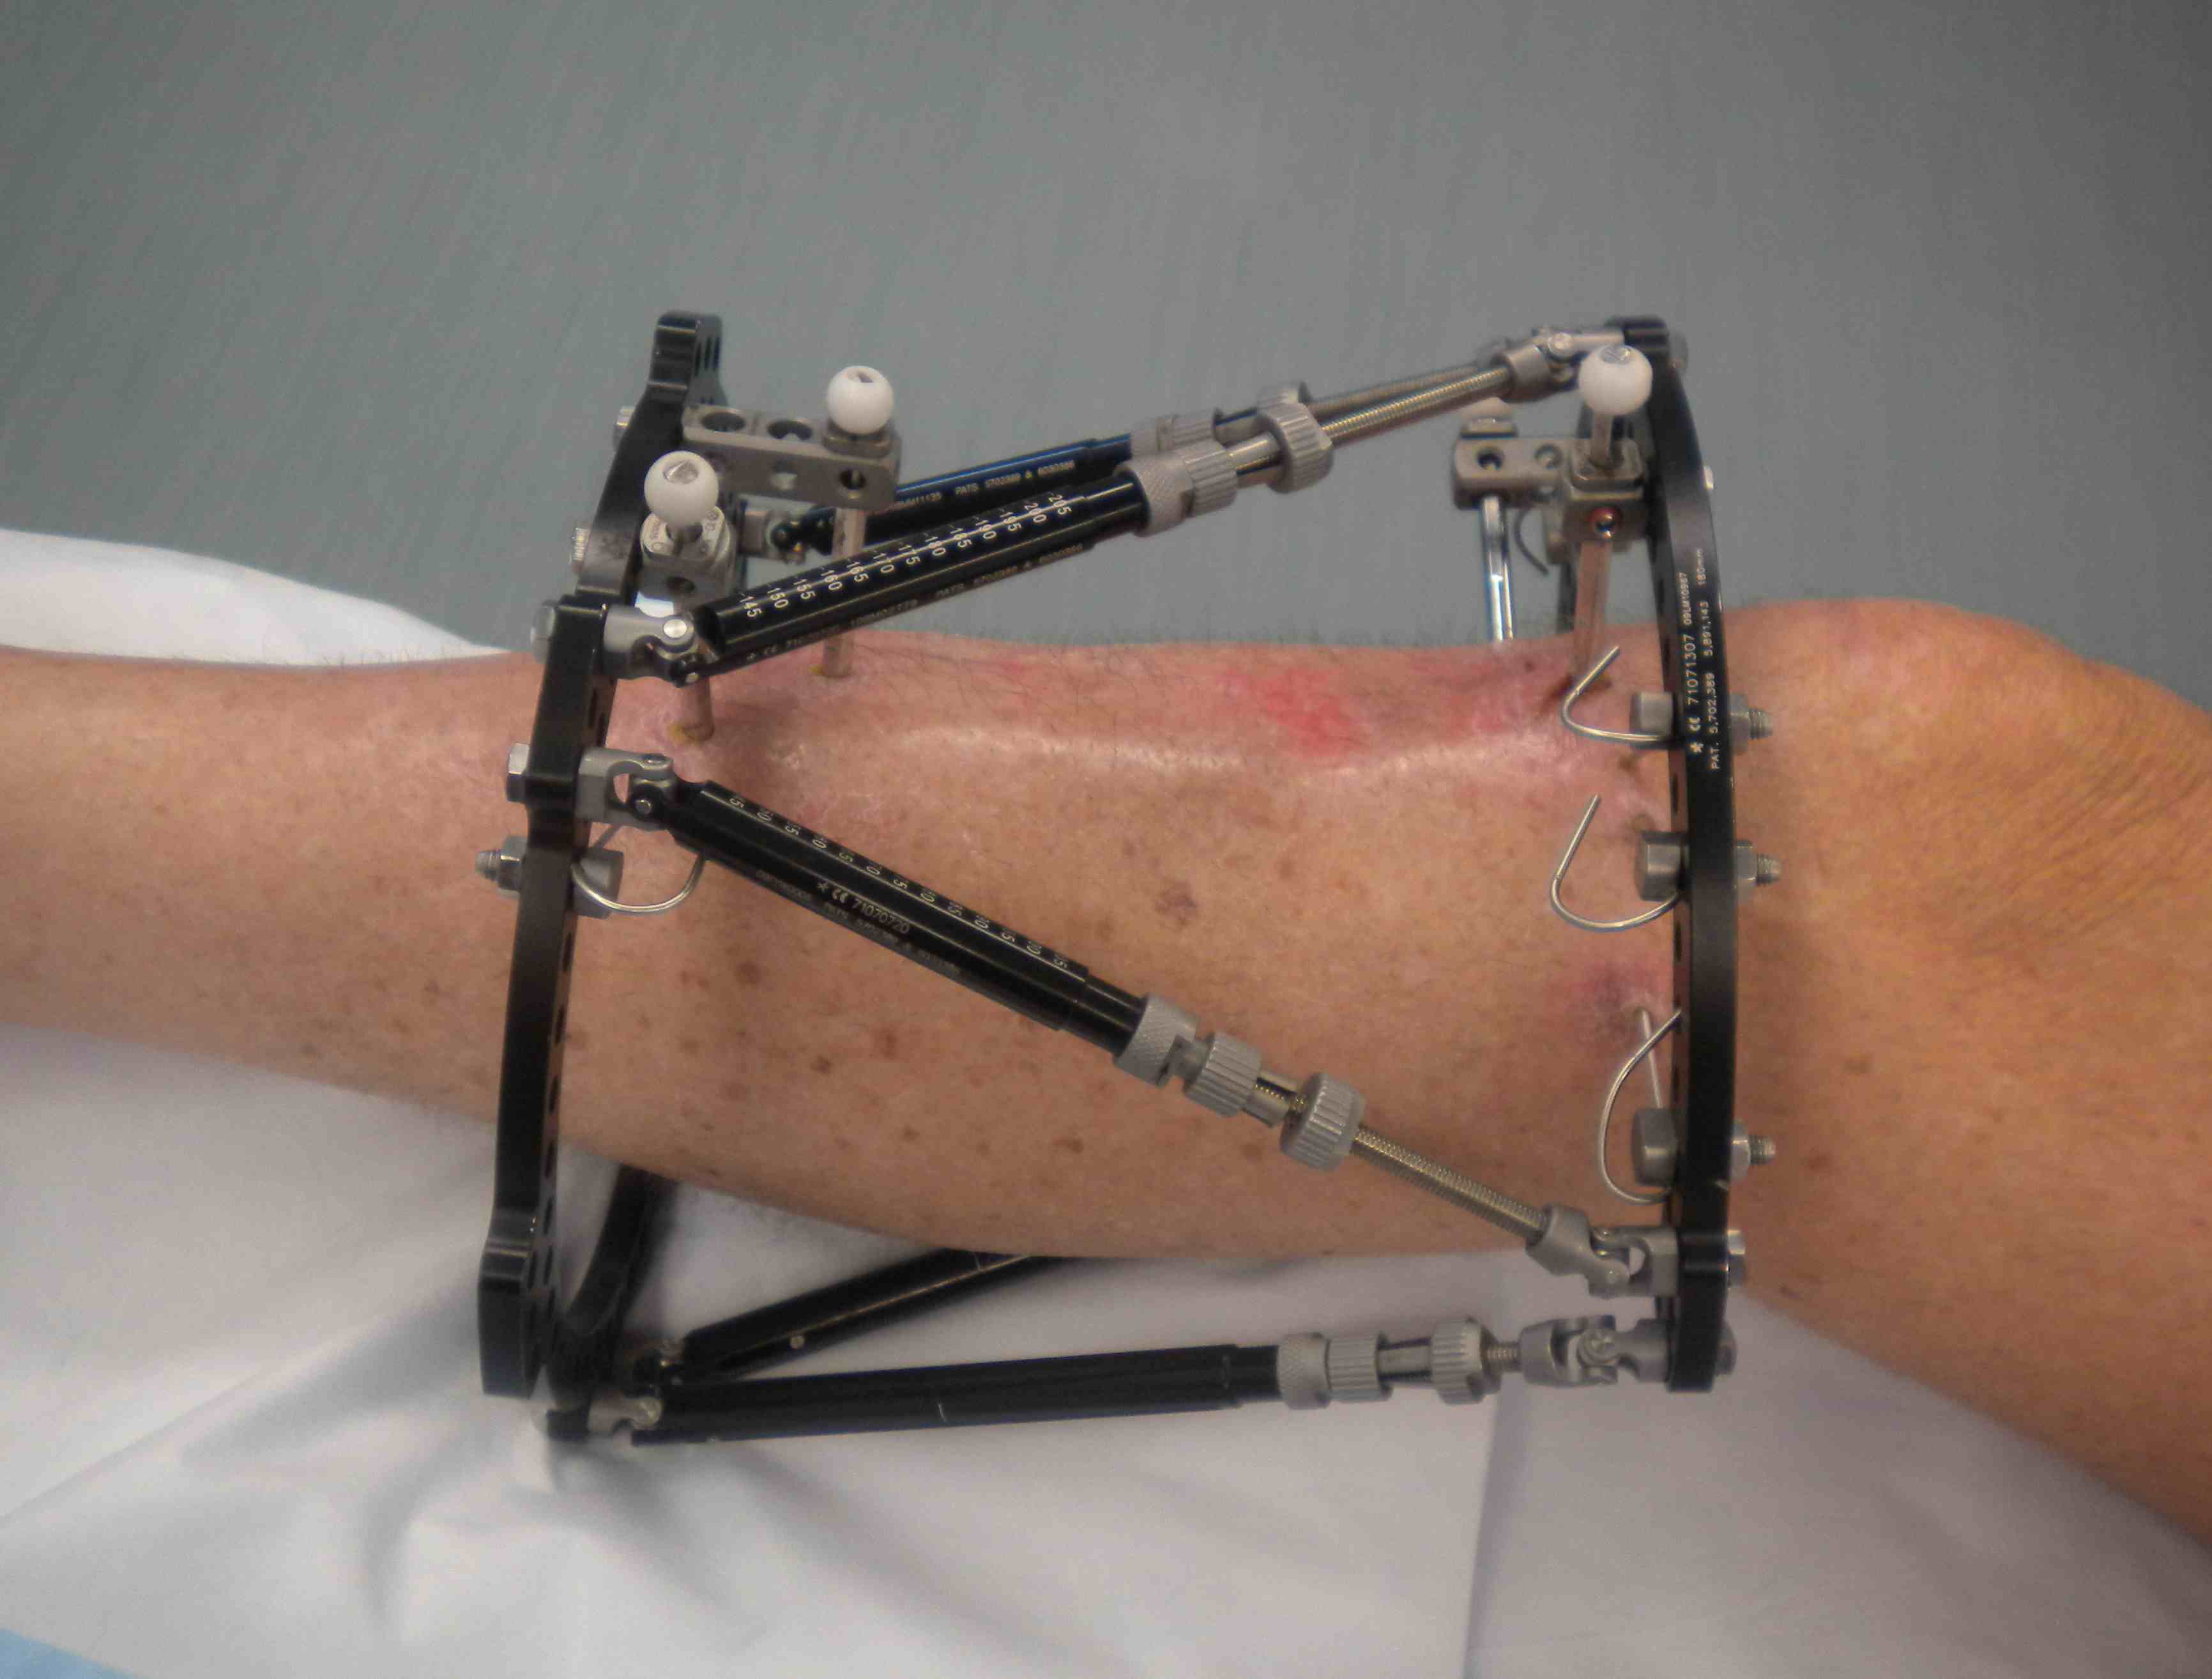

Deformity correction

Poor soft tissues

- prohibit ORIF

Non union

Infected non uniion

Malunion / deformity

Bone loss / bone transport / LLD